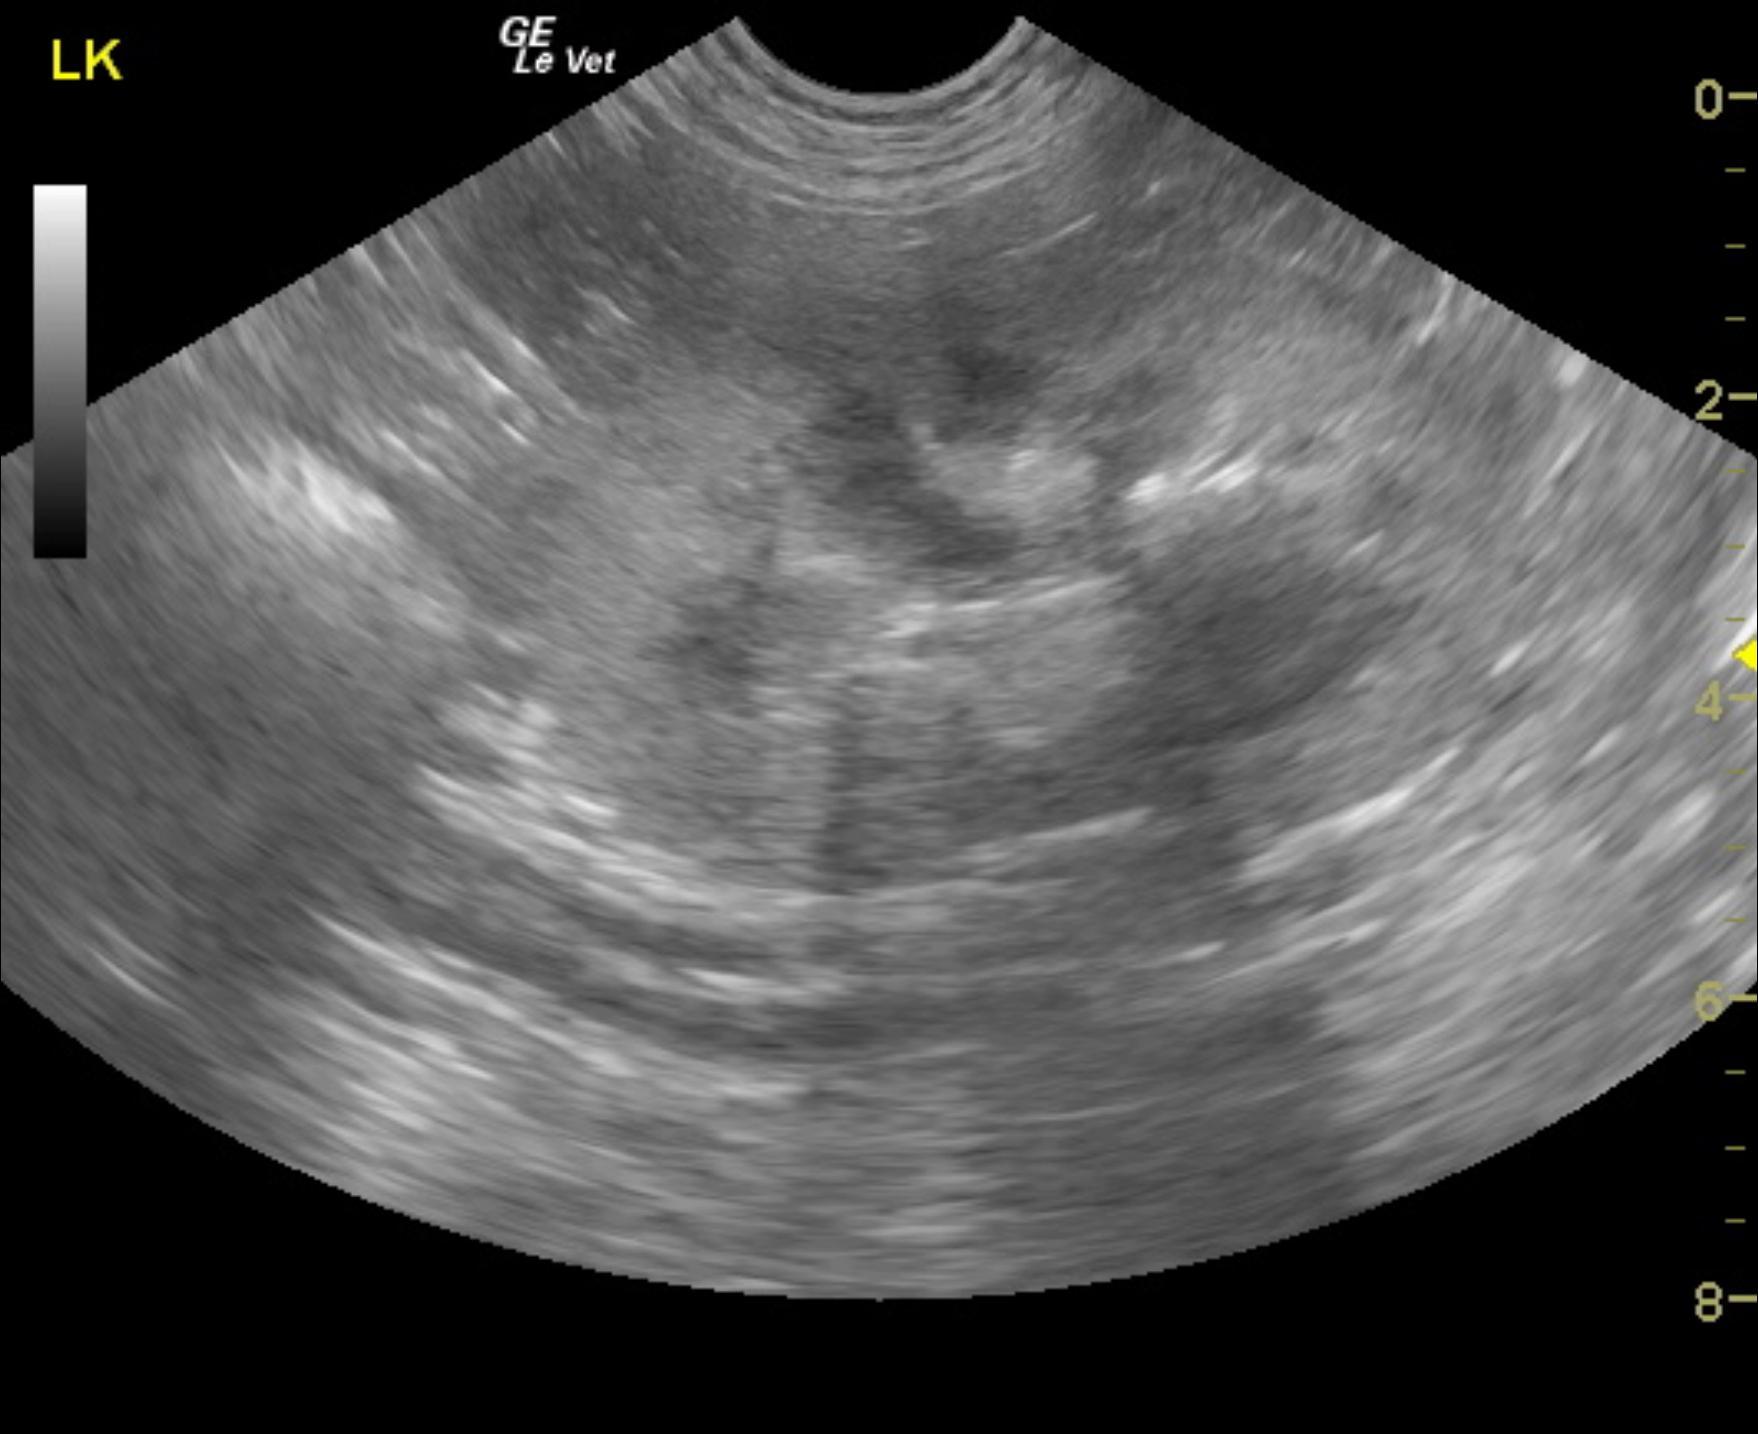

The patient is a canine English Bulldog, MN, 9 years, 67.5 lbs who was presented for vomiting and diarrhea. The patient is in renal failure. Urine specific gravity 1.017, 2+ protein, white count 11-20. Culture revealed E Coli. BUN 45, creatinine 3.6. Multiple, mild positives for Leptospirosis ( Leptospirosis titers positive. Pomona 1-200, Grippotyphosa 1-400. Autumnalis 1-200,

The patient is a canine English Bulldog, MN, 9 years, 67.5 lbs who was presented for vomiting and diarrhea. The patient is in renal failure. Urine specific gravity 1.017, 2+ protein, white count 11-20. Culture revealed E Coli. BUN 45, creatinine 3.6. Multiple, mild positives for Leptospirosis ( Leptospirosis titers positive. Pomona 1-200, Grippotyphosa 1-400. Autumnalis 1-200,